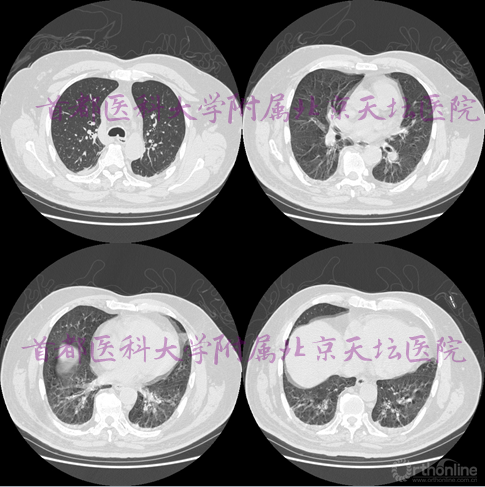

既往史:高血压20年,控制可,有冠心病史,有子宫切除及甲状腺切除史。无COPD及肺部疾病史。

多发性硬化、周围神经病变、呼吸系统疾病(血气分析、肺功能检查正常)

既往史:脑梗死11年,右侧肢体力弱。肺间质纤维化10年。高血压病、糖尿病、高脂血症。

• 肺间质纤维化 肺部感染 胸腔积液